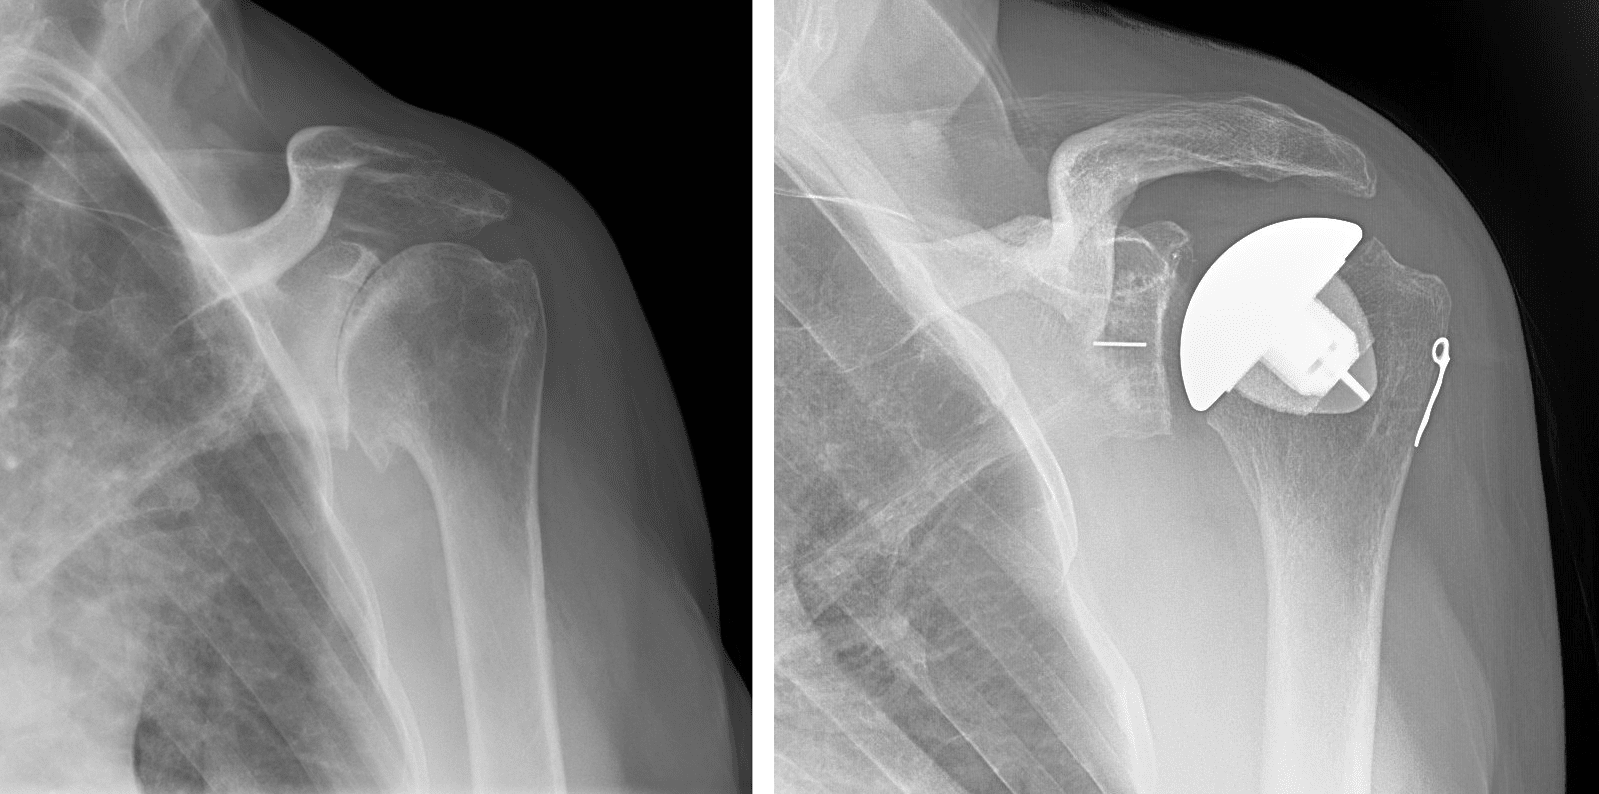

Shoulder Joint Replacement OrthoInfo AAOS

Shoulder Replacement arthroplasty and surgery How Long Does A Shoulder Replacement Hurt The surgery may not fully. Reduce or resolve pain in the shoulder. although rare, it's possible that shoulder replacement surgery won't lessen your pain or make it go away completely. how long does pain last after shoulder surgery? Improve range of motion and mobility. it’s difficult to say just how long your shoulder replacement will last. Experts. How Long Does A Shoulder Replacement Hurt.

Reverse Shoulder Replacement Medical Case Study Sydney Shoulder Unit How Long Does A Shoulder Replacement Hurt Experts estimate that most modern shoulder replacements will last for. Reduce or resolve pain in the shoulder. surgery aims to: Improve range of motion and mobility. how long does pain last after shoulder surgery? it’s difficult to say just how long your shoulder replacement will last. although rare, it's possible that shoulder replacement surgery won't lessen. How Long Does A Shoulder Replacement Hurt.

Shoulder Arthritis/Joint Replacement Rotator cuff tears Shoulder replacement complications How Long Does A Shoulder Replacement Hurt surgery aims to: Knowing what to expect after shoulder replacement can help you. although rare, it's possible that shoulder replacement surgery won't lessen your pain or make it go away completely. depending on the type of shoulder surgery and amount of repair work involved, pain may be expected for weeks or even months following the. Experts estimate. How Long Does A Shoulder Replacement Hurt.